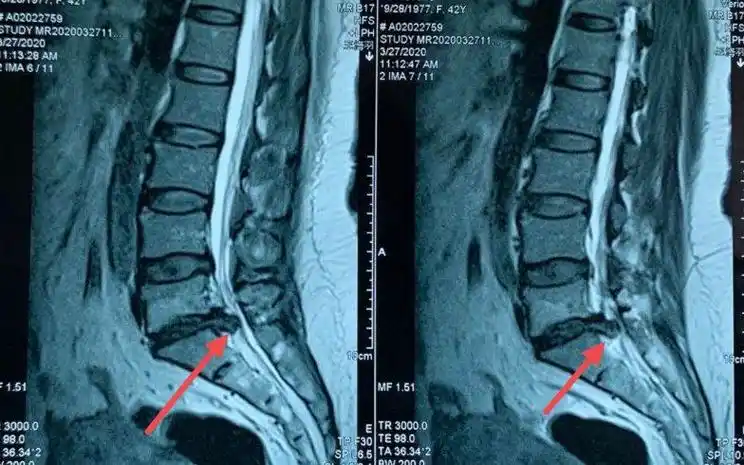

我的门诊病历:腰5骶1椎间盘突出症,保守治疗

术前磁共振显示腰5骶1椎间盘突出,神经根受压.

腰5骶1椎间盘突出

腰椎mri示:腰5/骶1神经根及硬膜囊明显受压.